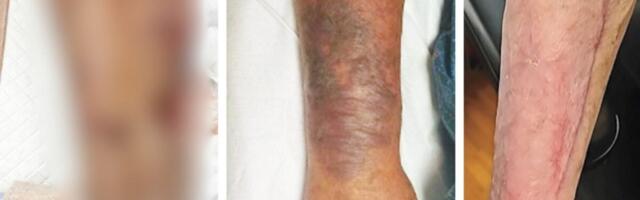

137 This Is What a Leg Ravaged by ‘Flesh-Eating’ Bacteria Looks Like

This Is What a Leg Ravaged by ‘Flesh-Eating’ Bacteria Looks Like

In a new case report, doctors detail how a 74-year-old man lost most of his right leg to a Vibrio vulnificus infection.